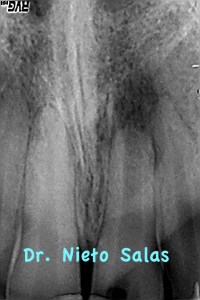

Acude a nuestra consulta un chico que tuvo un traumatismo hace años y que recientemente le ha salido una fístula.

le hacemos una Rx y vemos que se trata de un diente con ápices abiertos: